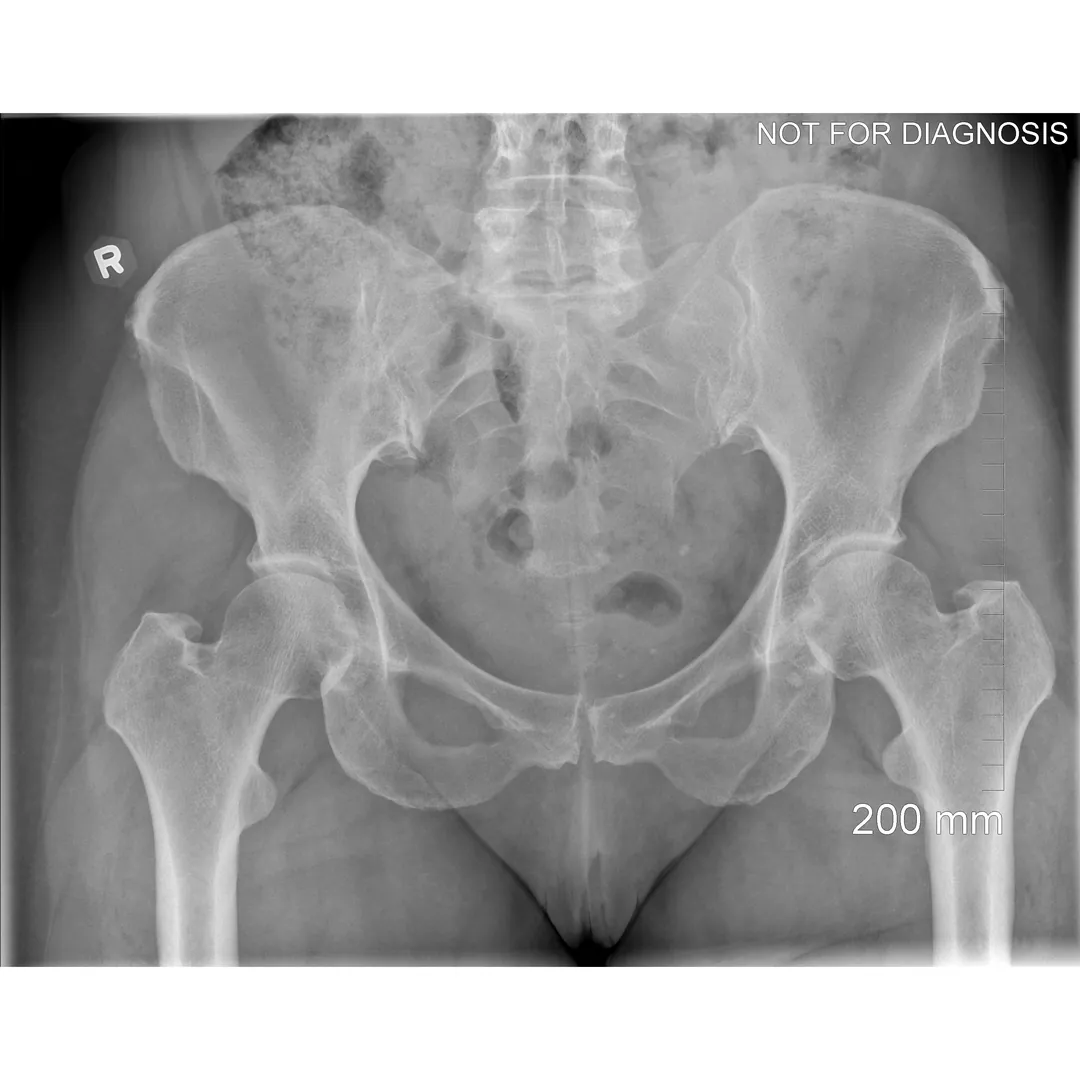

A total hip replacement (also called total hip arthroplasty) is a surgical procedure in which a damaged or worn hip joint is replaced with artificial components. The hip is a ball-and-socket joint, meaning the ball at the top of the thigh bone sits in a socket on the pelvis. During surgery, the damaged ball (femoral head) is replaced with a metal or ceramic ball attached to a stem, and the damaged socket is replaced with a metal cup lined with plastic, ceramic, or metal.

- The surgeon removes the damaged bone and cartilage and inserts the artificial joint